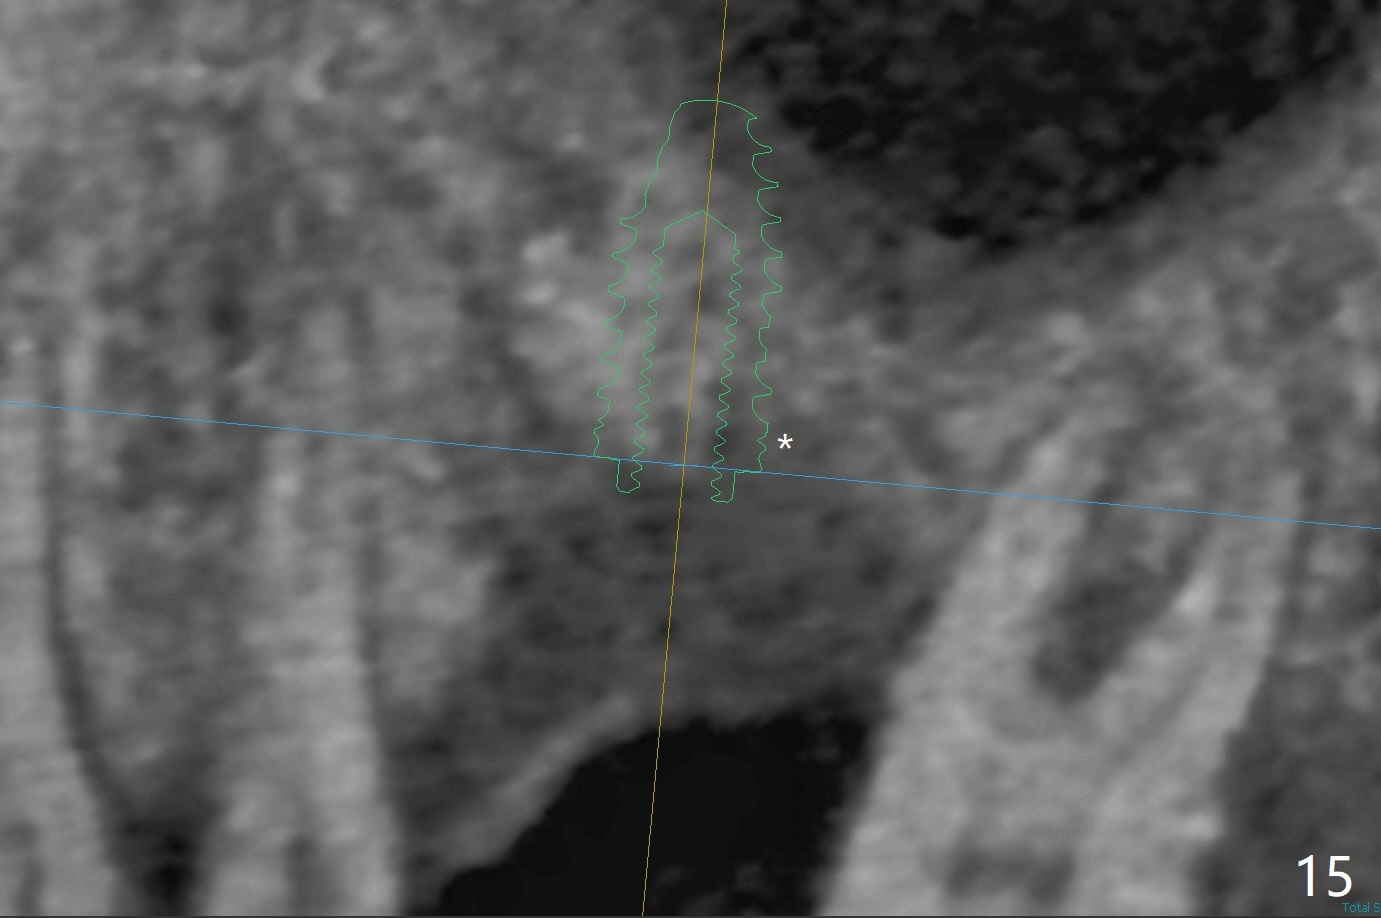

50岁男两年前不肯拔牙左上6(图一),现在要求及早拔除植骨(图二),几个月后与左下7一起植牙。我们准备深洗(图三橘黄色)后拔除残根(黑色),翻瓣后植入粘性骨块(红色)。为了解释手术步骤,给牙槽骨(A)做冠状切面,如图四黑色四方形,B:颊侧;P:腭侧;而粉红色代表牙龈(G)。图五红线表示切口,弯箭头:翻瓣,如图六。然后植入粘性骨块(图七:S)。盖上PRF膜(图八蓝线)以及不可吸收膜(图八绿线),最后使用PTFE缝线(图九:黑线)稍微关闭伤口,不至于压扁骨块。这样可行吗?需要使用tenting screw防止骨块塌陷?为了避免使用后者,索性直接植入植体(图十:绿色)和基台(浅蓝色),周围堆放骨粉(红色)。覆盖PRF膜(图十一:深蓝色),缝合(细线)。骨密度1200-1400单位;骨粘膜厚度4.2毫米,血供好(图十二;图十三:G: 牙龈)。翻瓣(图十四:箭头),植入植体(绿色),放置基台(粉红色)和骨粉(红色)。由于基台占据空间,缝合应该是松弛的,下面骨粉不易移位,在暴露螺纹附近愈合。Jennifer: flap surgery; since osteotomy will be created in a slope with most likely distal deviation, design the long axis of the implant mesial by 1 mm occlusally.

No Deviation 手术 提升 Xin Wei, DDS, PhD, MS 1st edition 09/29/2020, last revision 04/04/2021